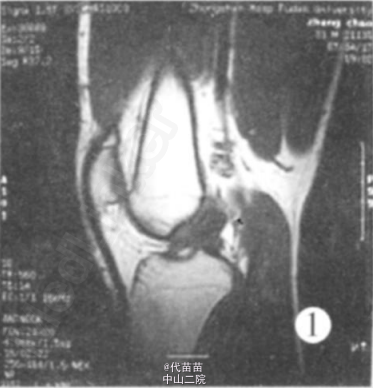

查体: 左膝关节无肿胀, 浮髌实验阴性, 左膝伸0° , 屈 130° 疼痛, McMurray 征阴性, 前后抽屉实验阴性, Lachman实验阴性。 MRI 报告示: (1) 左膝前交叉韧带囊肿。(2) 左膝关节腔内少量积液(图 1、2)。

初步诊断: 左膝前交叉韧带囊肿 手术所见: 患者在全麻下行左膝关节镜下前交叉韧带囊肿切除术。 取左膝髌旁内外侧常规入路, 见膝关节腔内无黏连,滑膜无增生肥厚及充血水肿, 股骨髁及胫骨平台软骨光滑, 内外侧半月板形态大小正常, 表面光滑无撕裂。 前交叉韧带后束中段可见一囊肿, 大小约 2 c m×1 c m×1 c m, 囊肿长轴与前交叉韧带长轴一致。 探针探查囊肿壁韧, 前交叉韧带完整性好,张力略低。 镜下手术切除囊肿, 小心咬除部分囊壁 , 用刨削器清除囊肿, 将切下的囊壁及囊肿碎片送病理。 囊肿切除后发现前交叉韧带松弛, 无张力。 遂决定行前交叉韧带重建, 镜下切断前交叉韧带, 打磨其股骨及胫骨止点。 在胫骨结节内侧 1cm, 关节线下 3 c m处作一纵形切口约 3cm, 切开缝匠肌筋膜,暴露半腱肌和股薄肌止点、分离, 用取腱器取出半腱肌和股薄肌肌腱各 1根, 然后, 四股编织后形成 12 c m长直径 8 mm的植入物备用, 在关节镜下用胫骨导向器调整角度为 45° , 打入导针, 检查导针位置在胫骨平台前 1/3处, 股骨止点在过顶处, 用8mm钻头, 扩胫骨隧道, 然后用股骨导向器再次确定股骨隧道开口, 后用 8 mm的钻头扩股骨隧道, 最后用带针导针将编织好的韧带引出, 股骨部分用强生Rigidfix固定, 胫骨处用强生Intrafix螺钉固定, 用探针检查植入前交叉韧带稳定后, 再次检查各个关节间室后, 无误注射透明质酸钠 5ml 防止黏连后, 关闭伤口, 加压包扎。囊肿病理检查结果: 纤维囊壁组织。诊断: 左膝前交叉韧带囊肿